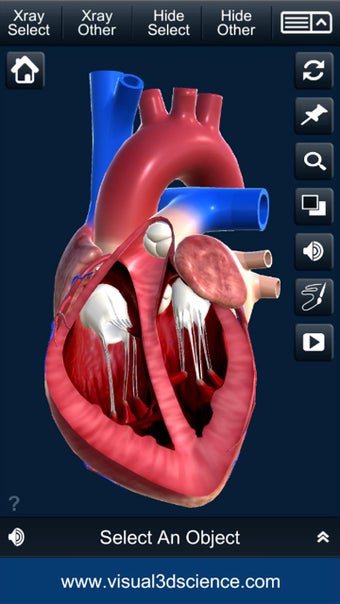

Es muy fácil de usar y muy interactiva. Puedes rotar 360°, hacer zoom y mover la cámara alrededor de un modelo 3D altamente realista.

El usuario puede seleccionar cualquier parte del corazón para ver su nombre o leer información relacionada.

Puedes seleccionar la vista de rayos X, ocultar y mostrar partes del corazón, así como ver animaciones en tiempo real, dibujar o escribir en la pantalla y compartir capturas de pantalla, pronunciación de audio para todos los términos de anatomía y más.